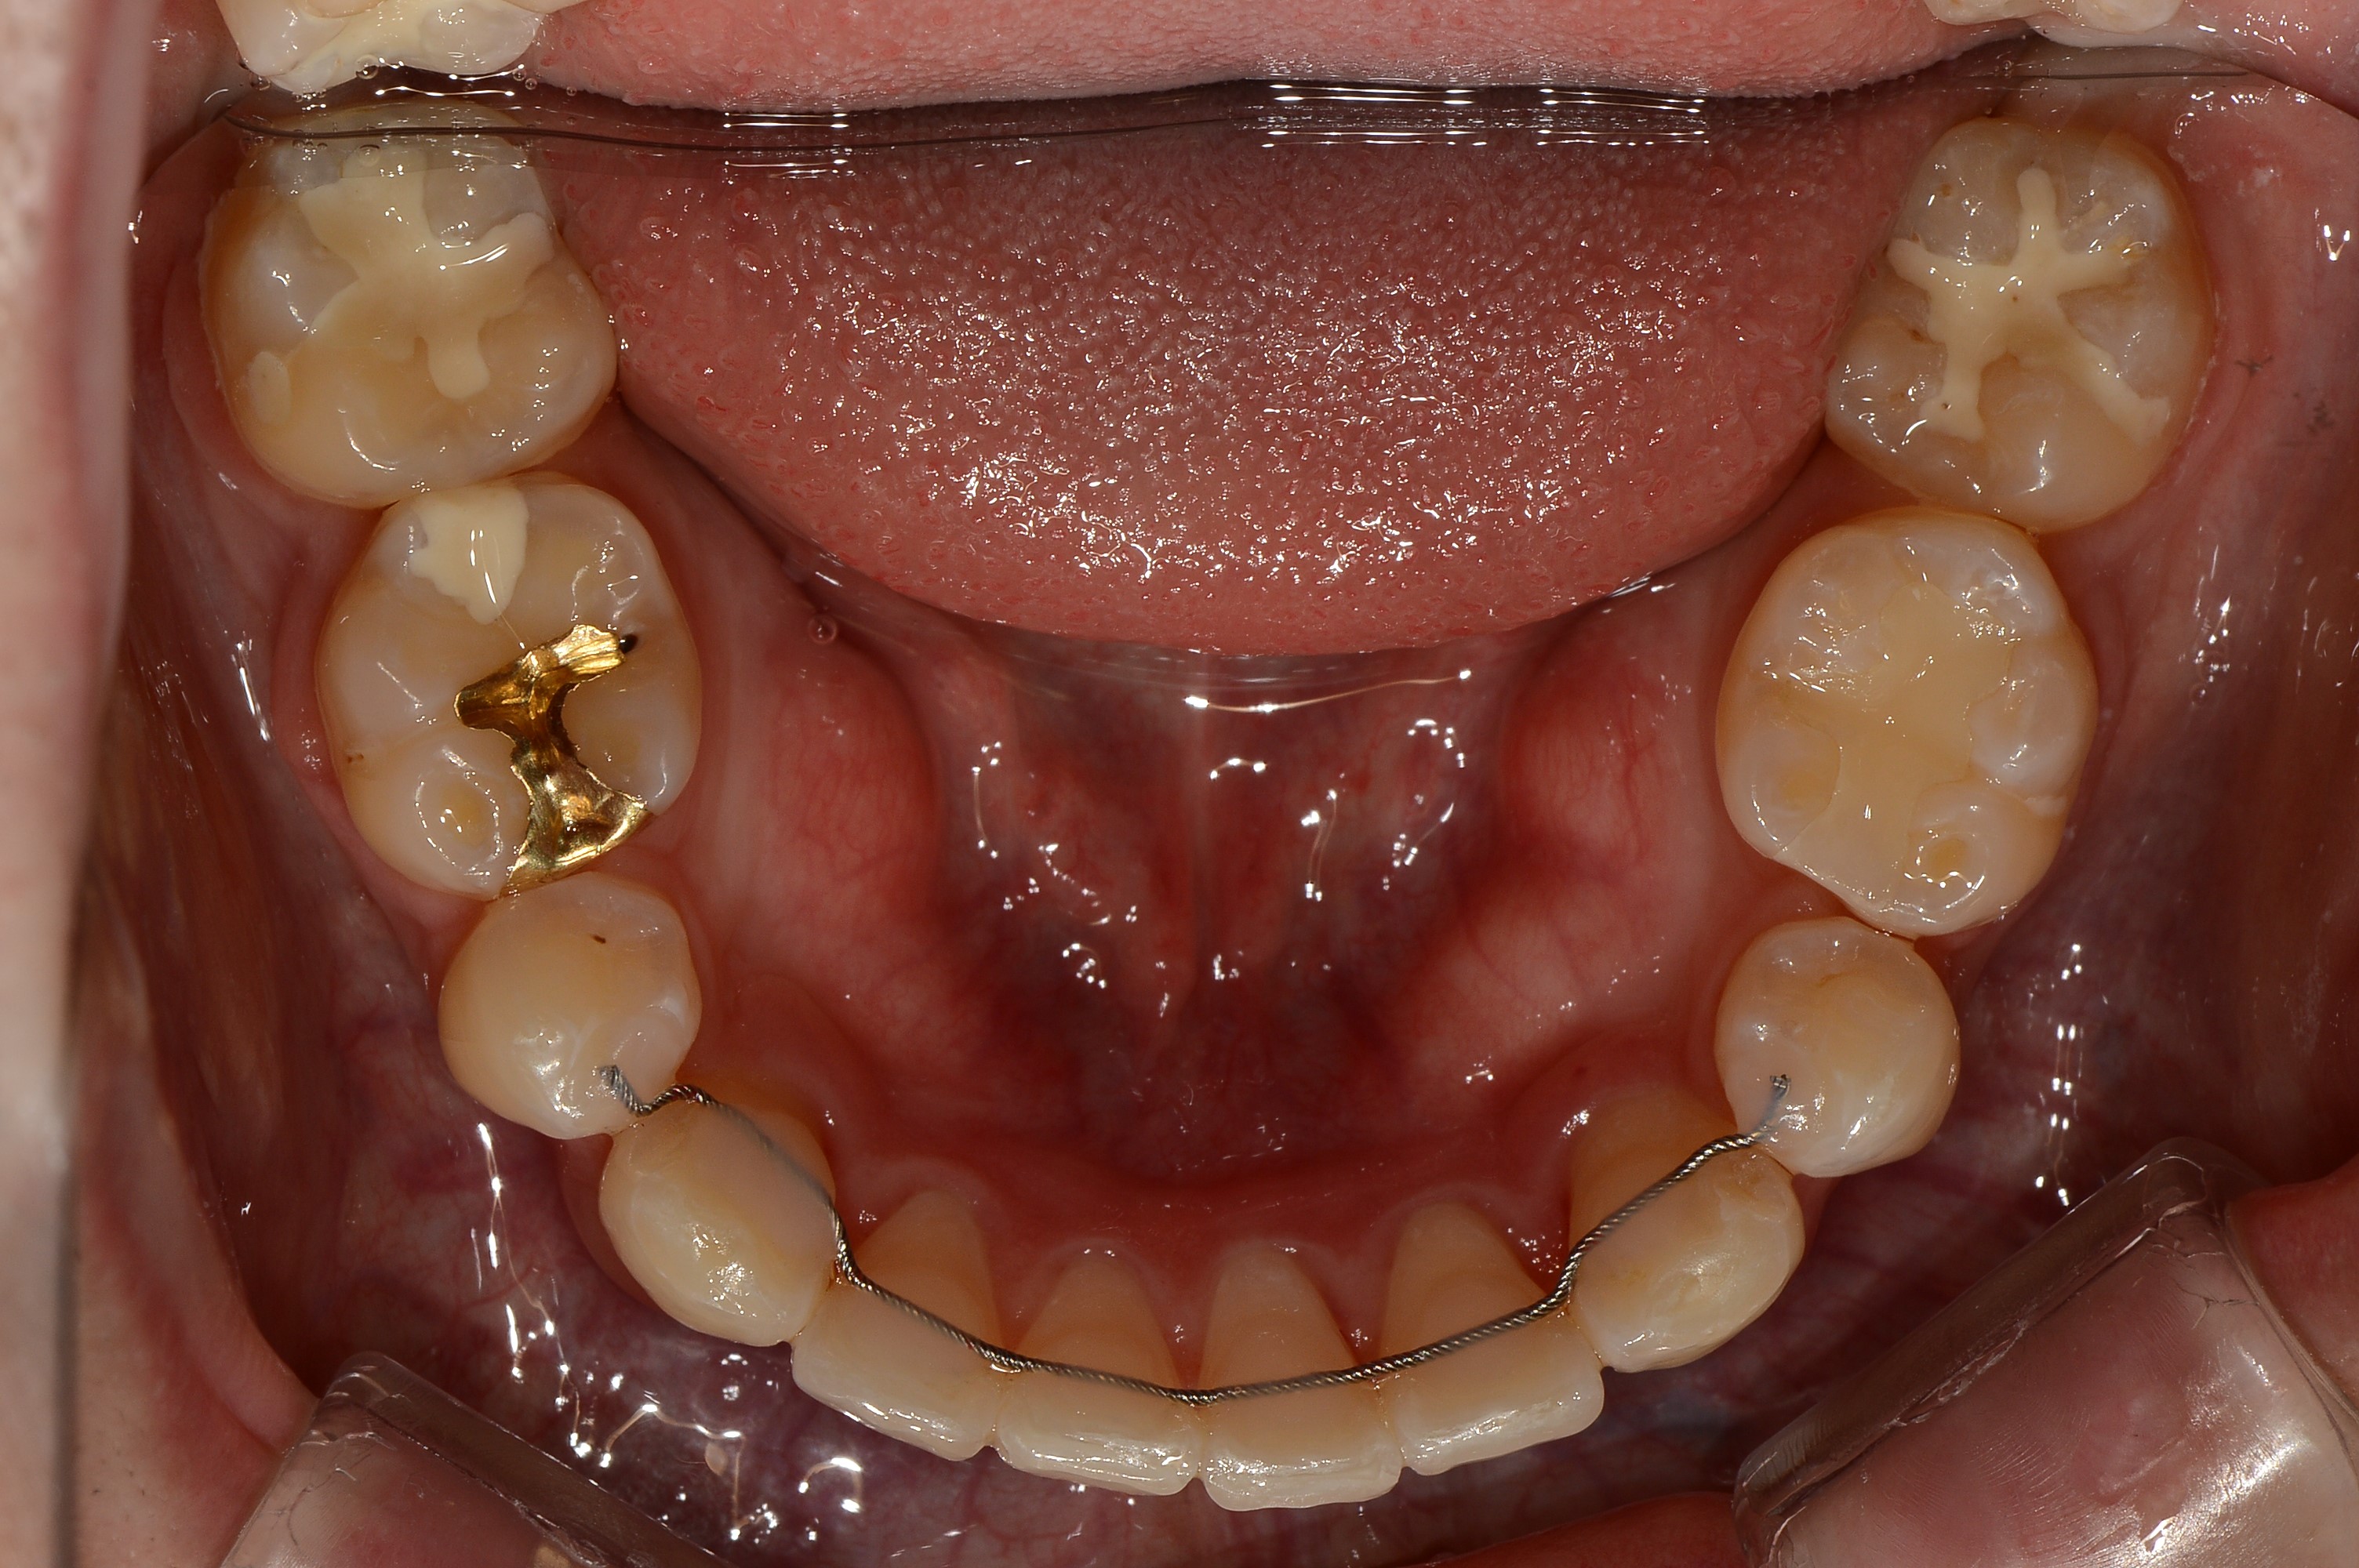

치료 후 사진입니다.